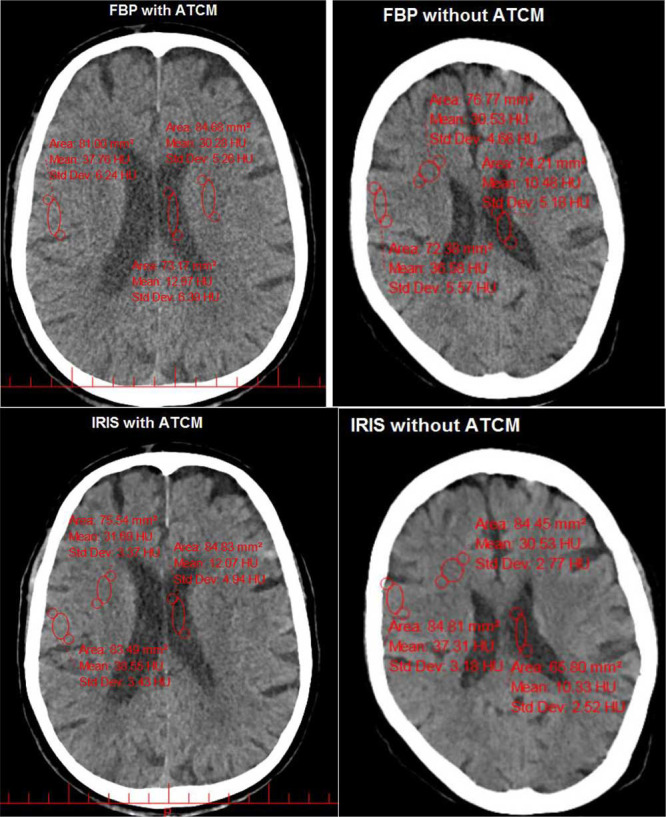

Material and methods: In this cross-sectional study, 200 patients underwent to brain CT scan, and images were then reconstructed using both FBP and IRIS. The CT Number (CTN), noise, and Signal-to-Noise Ratio (SNR) were computed for different tissues from CT images. The performance of two algorithms under different exposure conditions was evaluated using a water phantom. Two experienced radiologists assessed the image quality. Volume CT Dose Index (CTDIvol) and Dose Length Product (DLP) were recorded for each scan.

Results: FBP reconstruction exhibited higher noise and lower SNR compared to IRIS, both with and without ATCM. Noise levels significantly increased for FBP combined with ATCM. Subjective analysis showed higher performance for IRIS without ATCM compared to other approaches. The mean CTDIvol with and without ATCM was 20.04±3.33 and 36.37±4.65 mGy, respectively. In the phantom study, the noise with IRIS remained lower than that with FBP even with a 42% dose reduction.

Conclusion: IRIS algorithm can preserve the image quality when radiation dose is significantly reduced by ATCM in brain CT scan. Implementation of IRIS combined with ATCM is recommended for brain CT examinations.